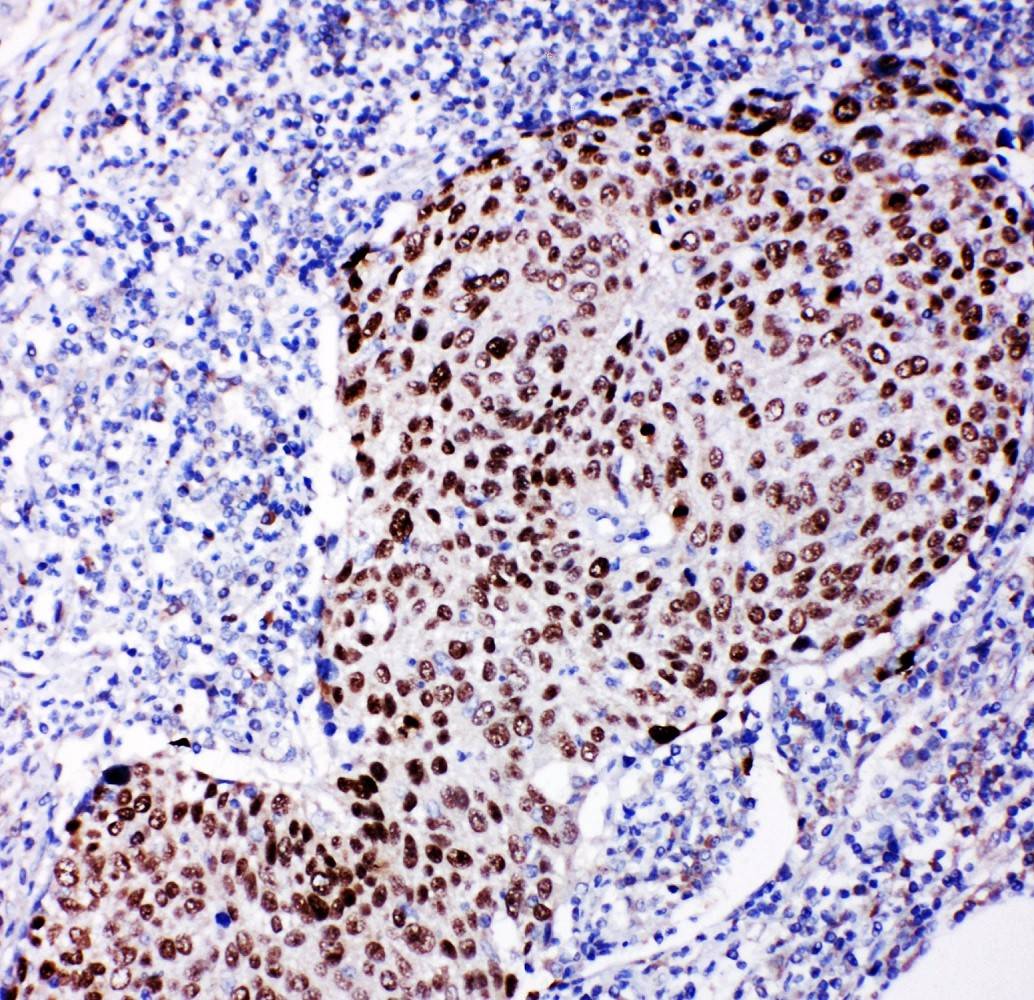

IHC analysis of p63/TP63 using anti-p63/TP63 antibody (BA1887).

p63/TP63 was detected in a paraffin-embedded section of human lung cancer tissue. Biotinylated goat anti-rabbit IgG was used as secondary antibody. The tissue section was incubated with rabbit anti-p63/TP63 Antibody (BA1887) at a dilution of 1:200 and developed using Strepavidin-Biotin-Complex (SABC) (Catalog # SA1022) with DAB (Catalog # AR1027) as the chromogen.